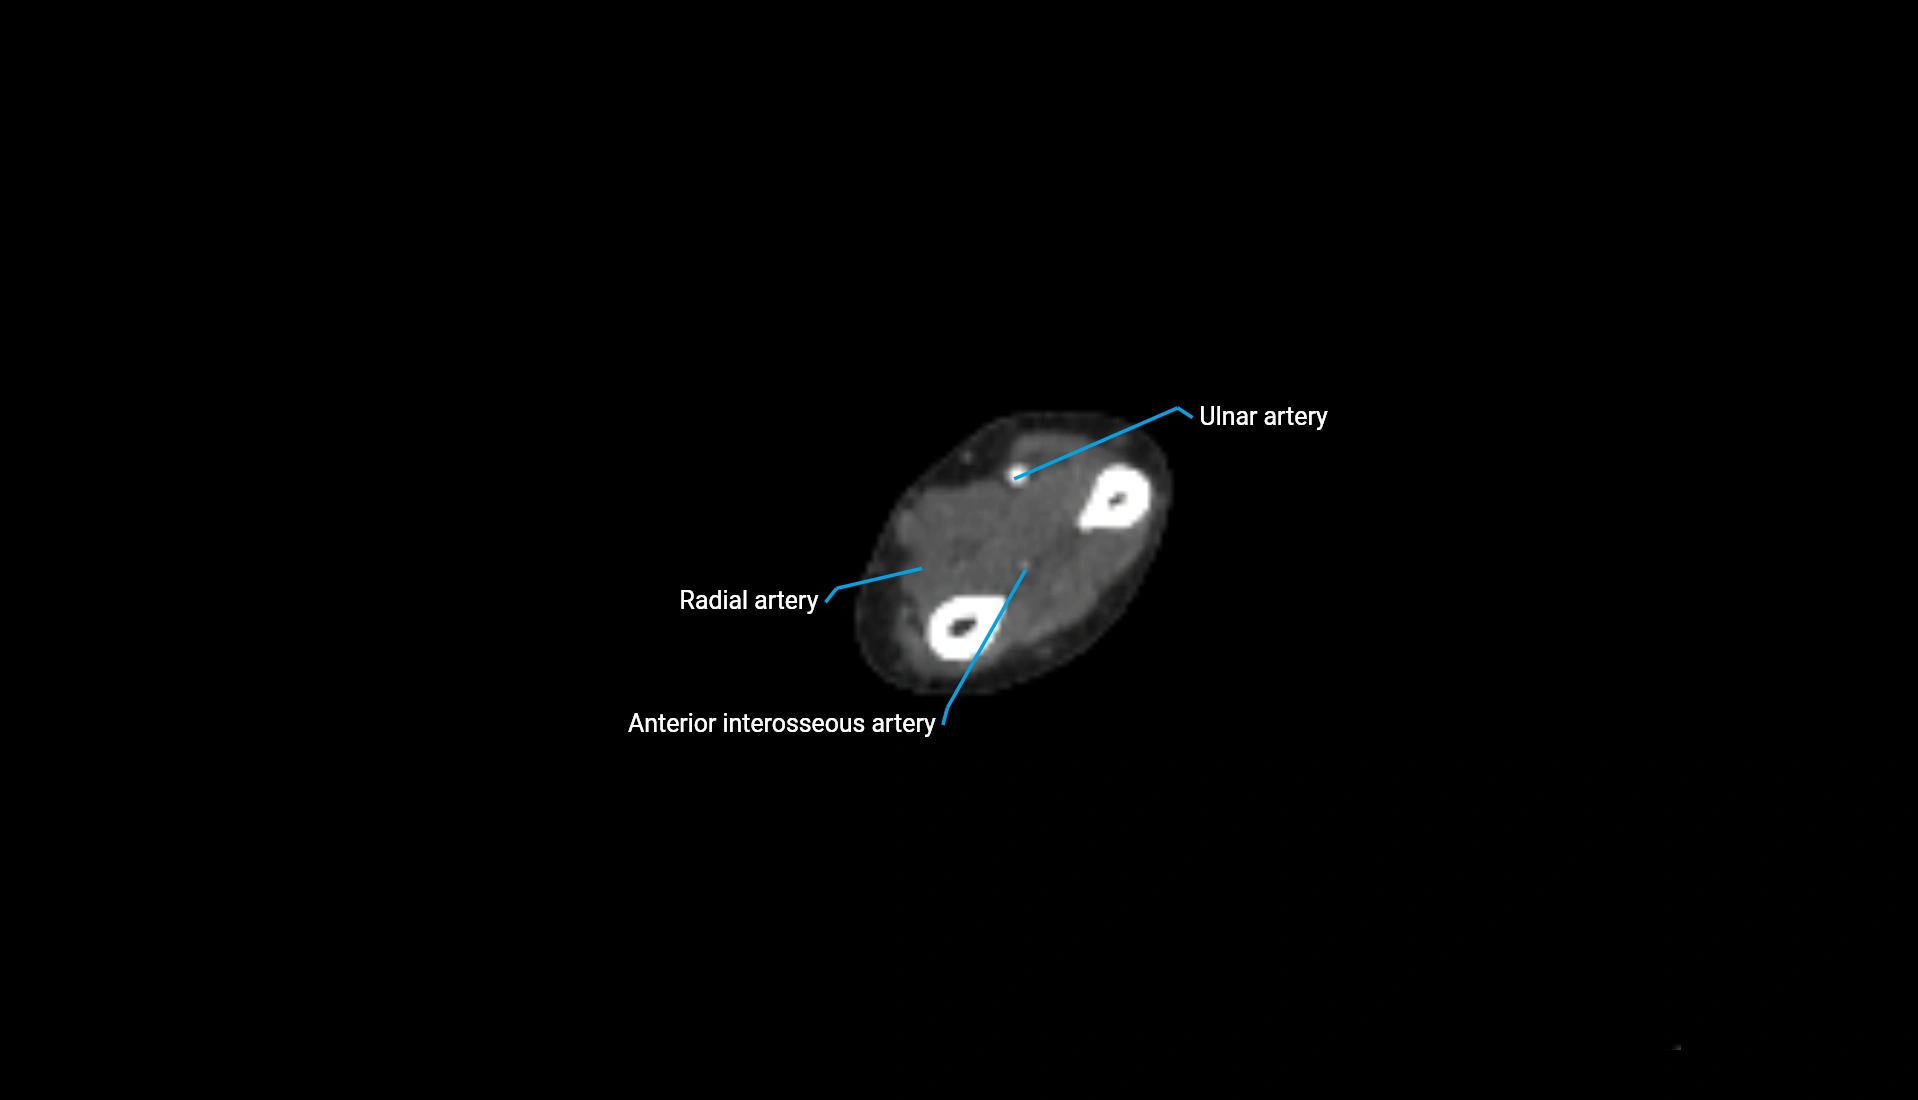

CT Appearance

Non-Contrast CT:

• Cortex: High-density, sharply defined

• Subchondral bone: Dense cancellous matrix

• Articular surface: Smooth concave contour articulating with the capitellum

• Excellent for evaluating bone integrity, alignment, and subtle fractures